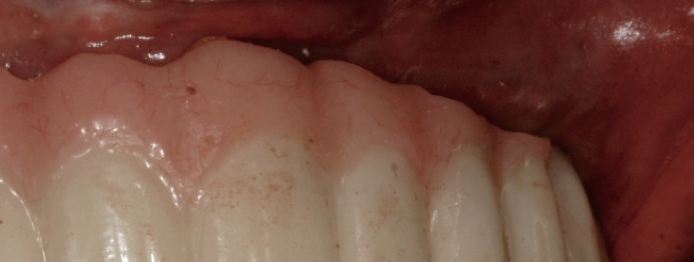

Improvement in tissue health around an implant after use of an oral irrigator.

Figure 1

There are a wide variety of such interdental products on the market. For implant patients, the author recommends choosing an oral irrigator that pulsates and has at least two tips: the universal tip and the dental implant tip with three tufts. A Tufts University School of Dental Medicine study found a water flosser with implant tip was 145% more effective than string floss around implants when used in conjunction with a manual toothbrush.9 Significant reduction of gingival bleeding at 2 weeks and 30 days, respectively, were reported.9 Improvement in the health of tissues around implants can be seen in one patient who presented with inflammation around an implant (Figure 1), and another patient with a full-arch prosthesis that now has minimal-to-no plaque around both the top and bottom peri-implant tissues (Figure 2).